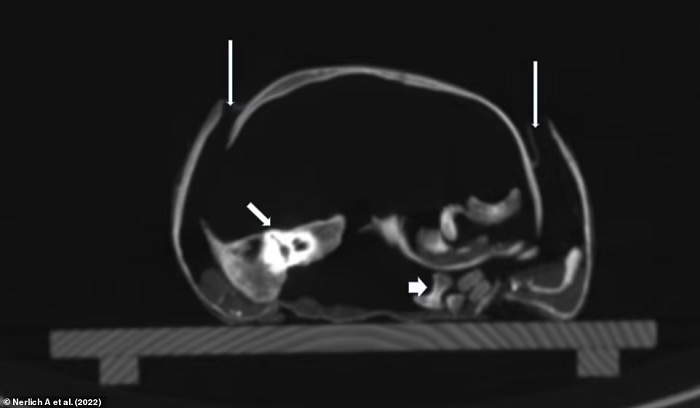

Tuy nhiên, kết quả chụp CT thể hiện xương sườn của cậu bị biến dạng, dấu hiệu của căn bệnh chuyển hóa xương (Metabolic Bone Disease - MBD) thường được thấy trong các trường hợp mắc bệnh còi xương nghiêm trọng. Hình ảnh chụp cắt lớp cũng cho thấy tình trạng đặc trưng của bệnh viêm phổi.

Đối với các nhà nghiên cứu, điều này cho thấy rằng mặc dù đứa trẻ mới biết đi đã được cho ăn đủ để tăng cân nhưng vẫn bị suy dinh dưỡng, hậu quả của việc bị giữ trong nhà không cho tiếp xúc với ánh nắng mặt trời khiến cơ thể cậu bé bị thiếu vitamin D.

Với những bằng chứng thu thập được, nhóm nghiên cứu kết luận rằng, cậu bé đã chết vì bệnh viêm phổi cũng như cơ thể thiếu hụt những nguồn dinh dưỡng cần thiết.